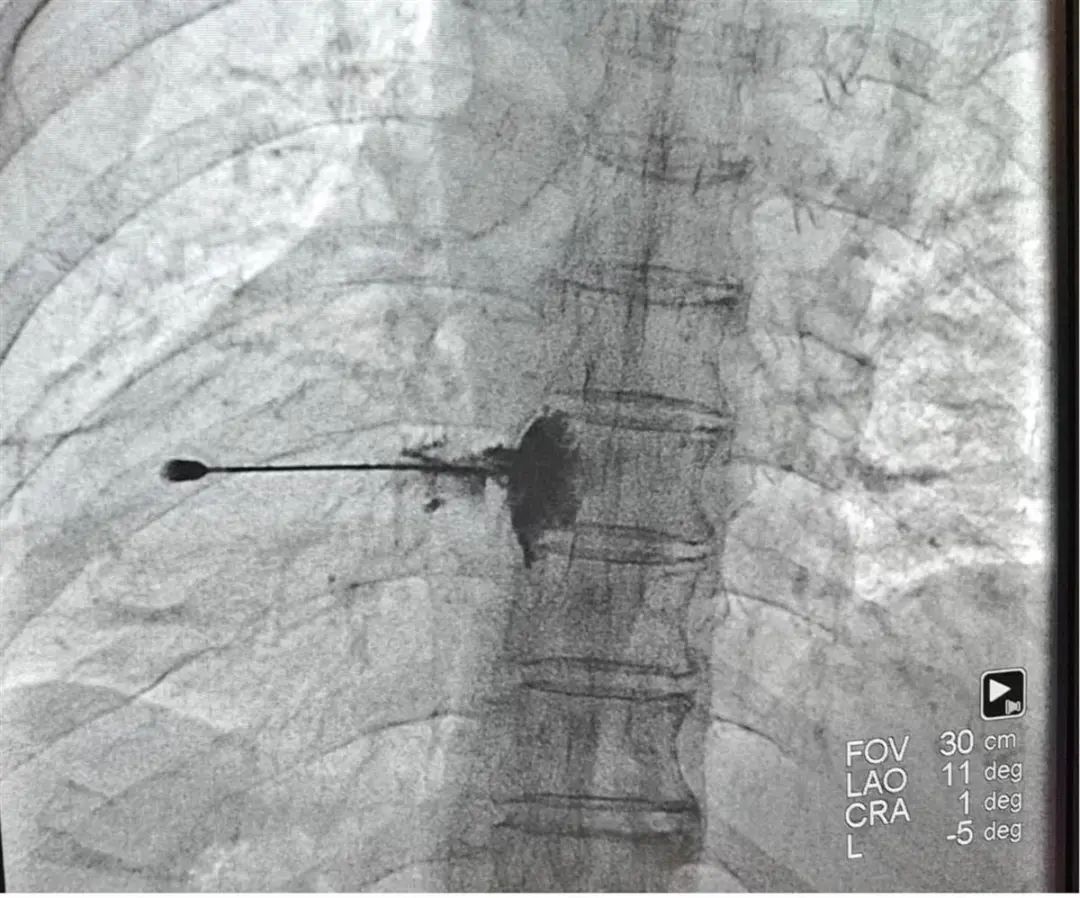

术中DSA指引下胸背神经节神经显影。

12月9日,疼痛科团队在局部麻醉下对陈先生进行了胸背神经节射频控制。半小时后,手术顺利完成。手术后,陈先生恢复良好,很快就可以出院了。